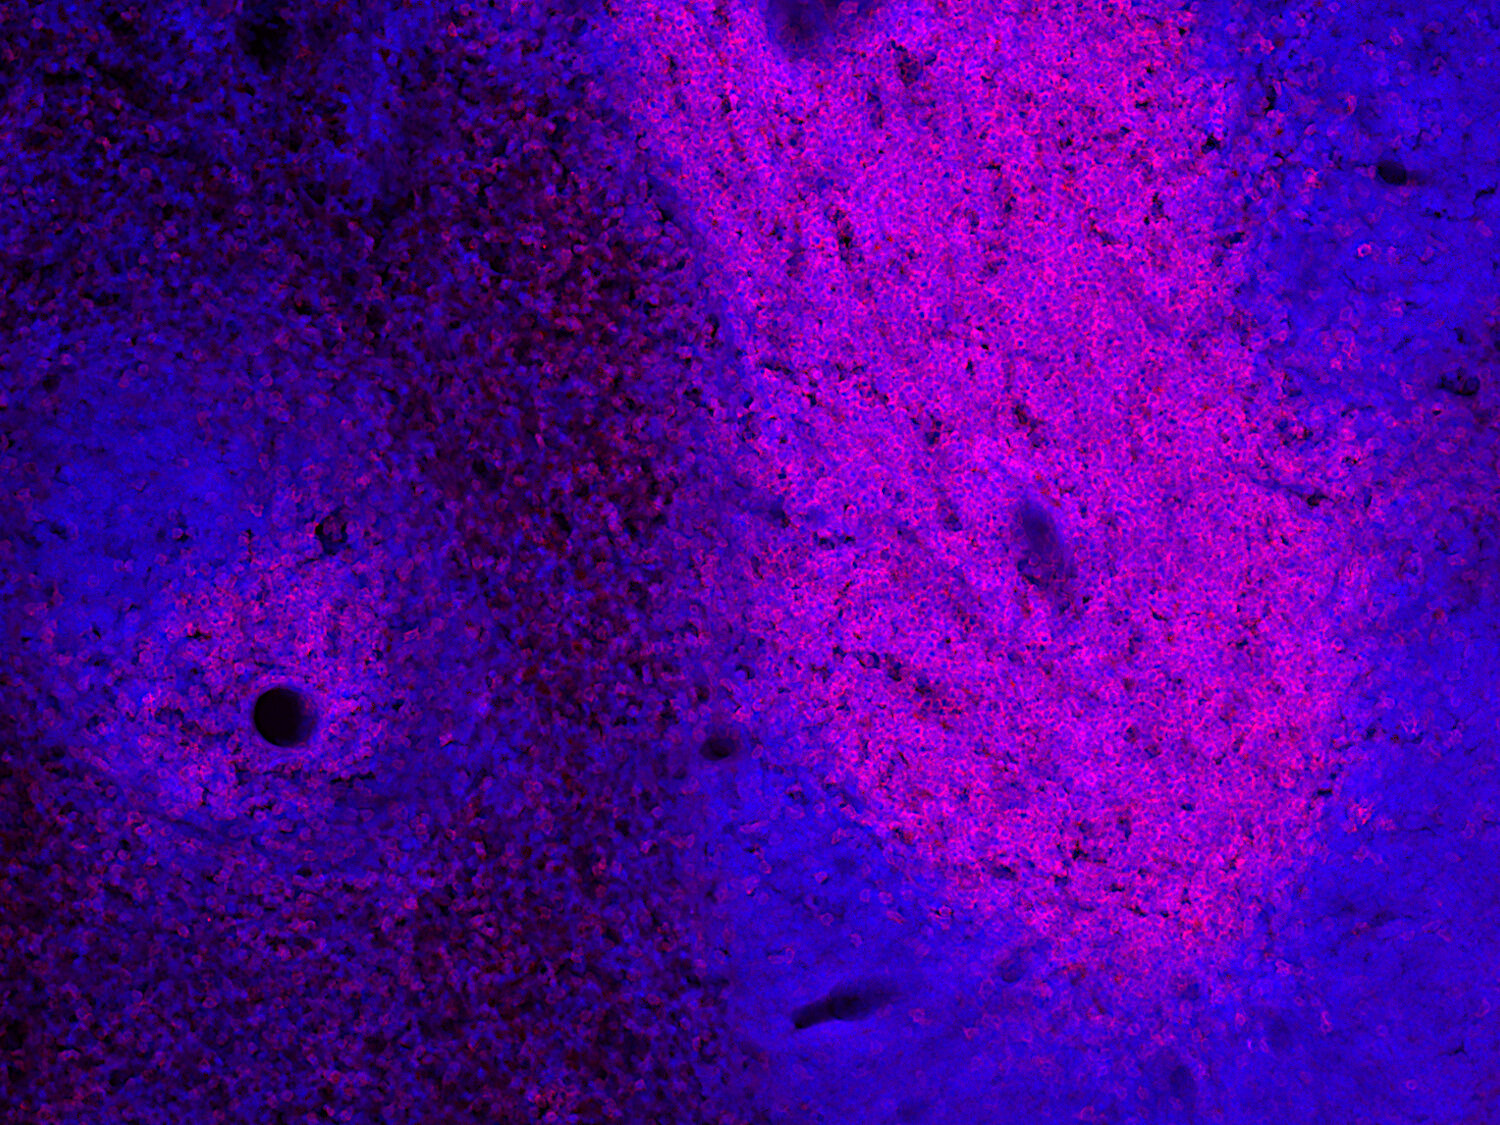

Detection of CD3e positive cells in FFPE mouse spleen section

IHC: 1 : 100 (see remarks) gallery

IHC-P (FFPE): 1 : 100 gallery

IHC: Antigen retrieval with citrate buffer pH 6 is required.